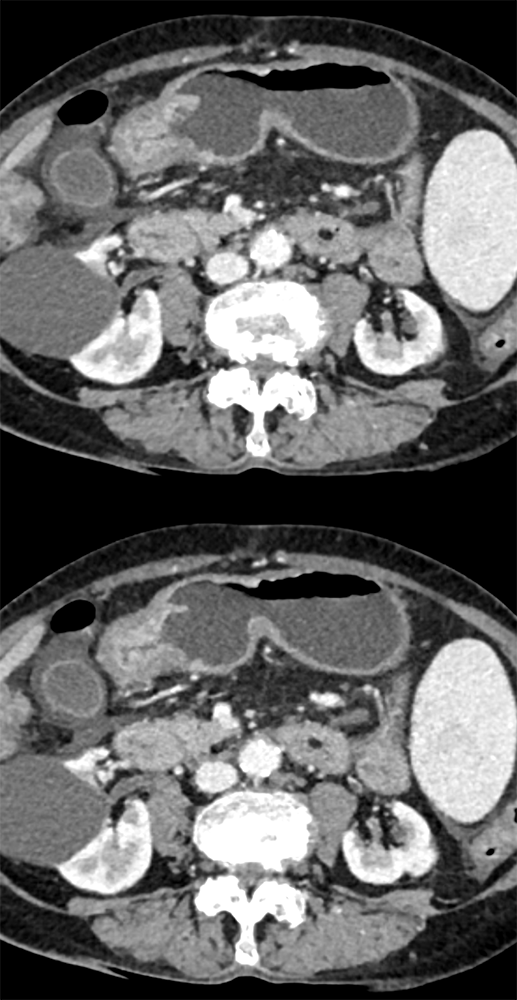

“In our patient, the findings of prominent mucosal folds extending from the pylonic channel on upper gastrointestinal series and the thickened antral wall on CT scans correlate well with the known pathologic appearance of gastnic antral vascular ectasia. Histologically, antral thickening results from a combination of foveolar and fibromuscular hyperplasia. Grossly, the antral fold prominence appears to result from bunching of the mucosa in the thickened, hypercontractile antrum.” Gastric antral vascular ectasia ("watermelon stomach"): radiologic findings. Urban BA, Jones B, Fishman EK, Kern SE, Ravich WJ. Radiology. 1991 Feb;178(2):517-8. |

Watermelon stomach (WMS), or gastric antral vascular ectasia (GAVE) ![]() |

“Gastric antral vascular ectasia primanily affects women (9:1 female-to-male ratio) aged 56-76 years, and is associated with liver cirrhosis (37%) and achlorhydnia (35%). The usual symptoms are iron-deficiency anemia and melena due to chronic gastrointestinal bleeding from the dilated, superficial, and easily traumatized vessels. Antrectomy is curative, but endoscopic treatment with heat probes or lasers has shown promise.” Gastric antral vascular ectasia ("watermelon stomach"): radiologic findings. Urban BA, Jones B, Fishman EK, Kern SE, Ravich WJ. Radiology. 1991 Feb;178(2):517-8. |